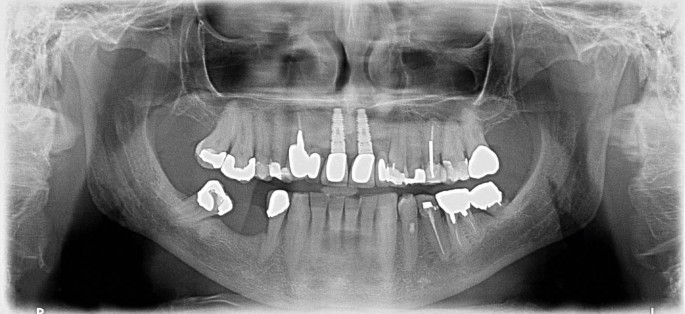

The worrying effect which crowning has on canines should not make us blinded to other aspects of guidance. The orthopantograph presented in Figure 1 is of a male patient in his late sixties who attended the clinic of one of the authors (NW), as he wished to consider implants to replace the missing teeth in the lower right molar area. He had previously consulted several colleagues who had suggested different treatment plans, among these being crowning the lower right second molar tooth, which was heavily restored, and orthodontically uprighting the lower right molar which had tipped mesially. Of note to this discussion was the cantilever bridge replacing the upper right lateral incisor using the upper right canine for support (Fig. 1) - this had, according to the patient's recollection, been in place for over 30 years. Considering the data from the studies outlined earlier, such good performance would appear quite remarkable, until the patient's occlusal scheme was examined. Such examination indicated that there was a working side interference on the lower right second molar and, as a result, the (crowned) upper right canine did not come into occlusal contact during lateral movements, as it was protected by the lower right second molar. Any treatment to this tooth, such as crowning or uprighting, would change the occlusal scheme to one of canine guidance which would, in our view, have been catastrophic for the canine. Accordingly, we advised the patient to save his money for when the canine did fail, either on its own or following the fracture of the lower right molar.

Orthopantomograph of male patient discussed in the text. Of note are the tilted 47 and the cantilever bridge from the root-filled/post-crowned 13 replacing 12